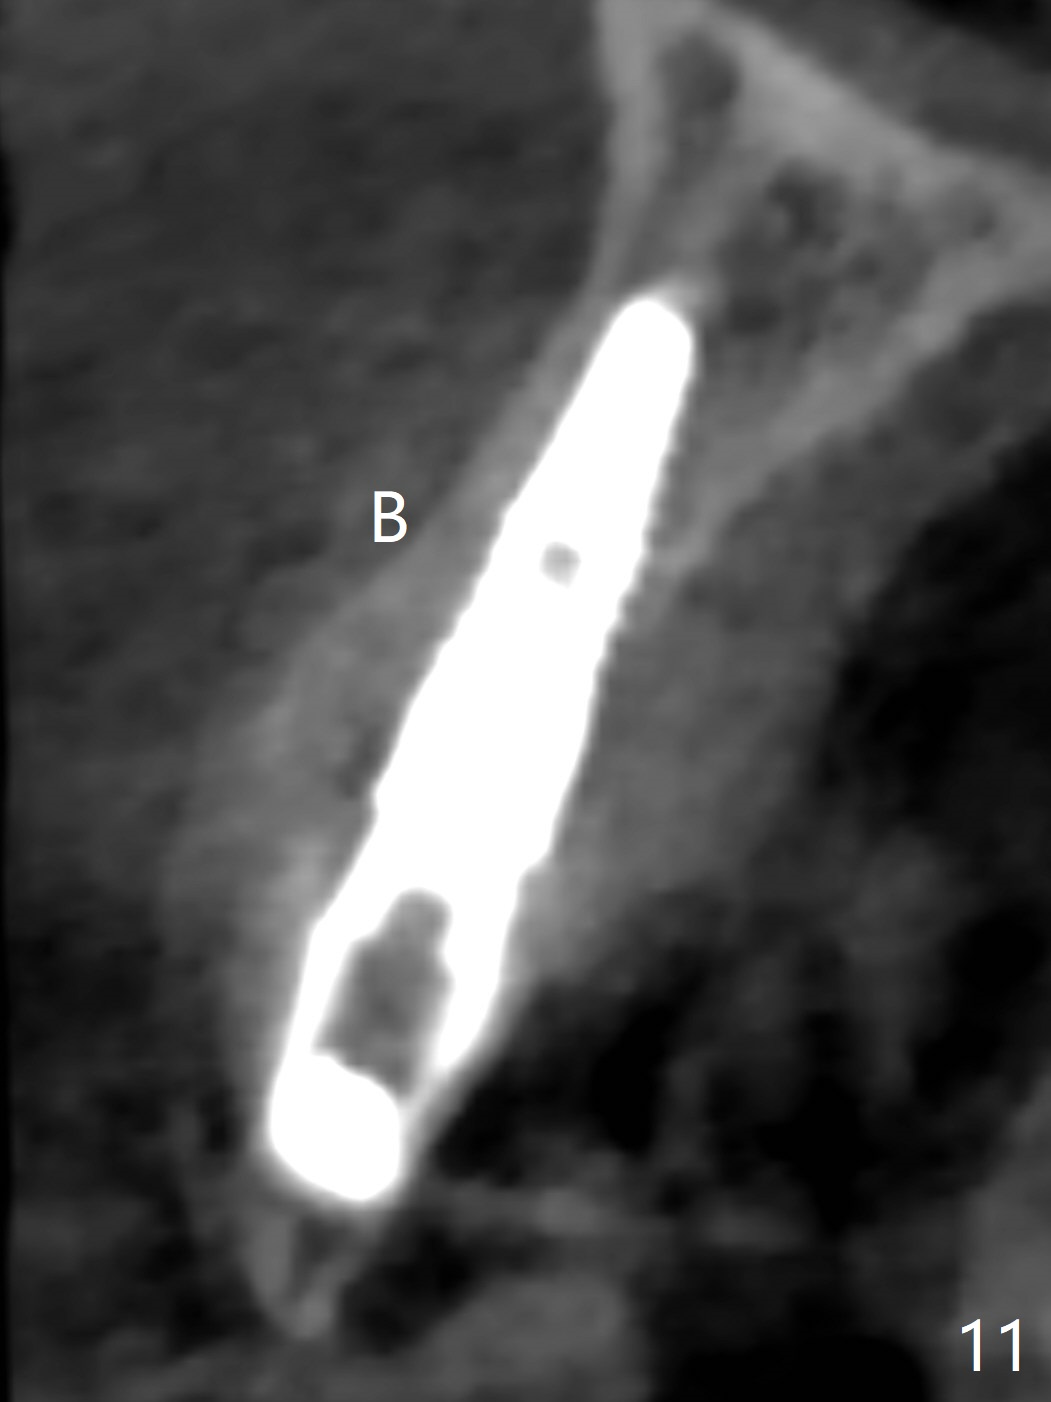

When the patient returns, the crown at #10 has displaced incisally (Fig.1,2 arrow). The initial depth is 15 mm (Fig.3, palatal gingival margin). After a 3.8x12 mm SM implant is placed (Fig.4), allograft is packed in the peri-implant space (*, as compared to Fig.3) and a 3.9x4(3) mm abutment is placed (A). More allograft is placed in the peri-abutment space (Fig.6 *). The existing crown (Fig.4,5 C) is hollowed, relined (R) and used as an immediate provisional (Fig.7-9). The patient is pleased with the appearance of the apically-repositioned provisional (Fig.7 arrow). She returns for impression 3.5 months postop (Fig.10). After change of abutment to 3.9x4(4.5) mm and new provisional, impression is retaken 5 months postop (Fig.11,12). It appears that the implant is palatally placed and a little large for the site (Fig.11 (B: buccal); Fig.12 (^: thin layer of the palatal plate)). If an angled abutment were used, a screw-retained crown might have been feasible. Due to the new provisional, the gingiva looks healthy when a permanent crown is cemented (Fig.13).